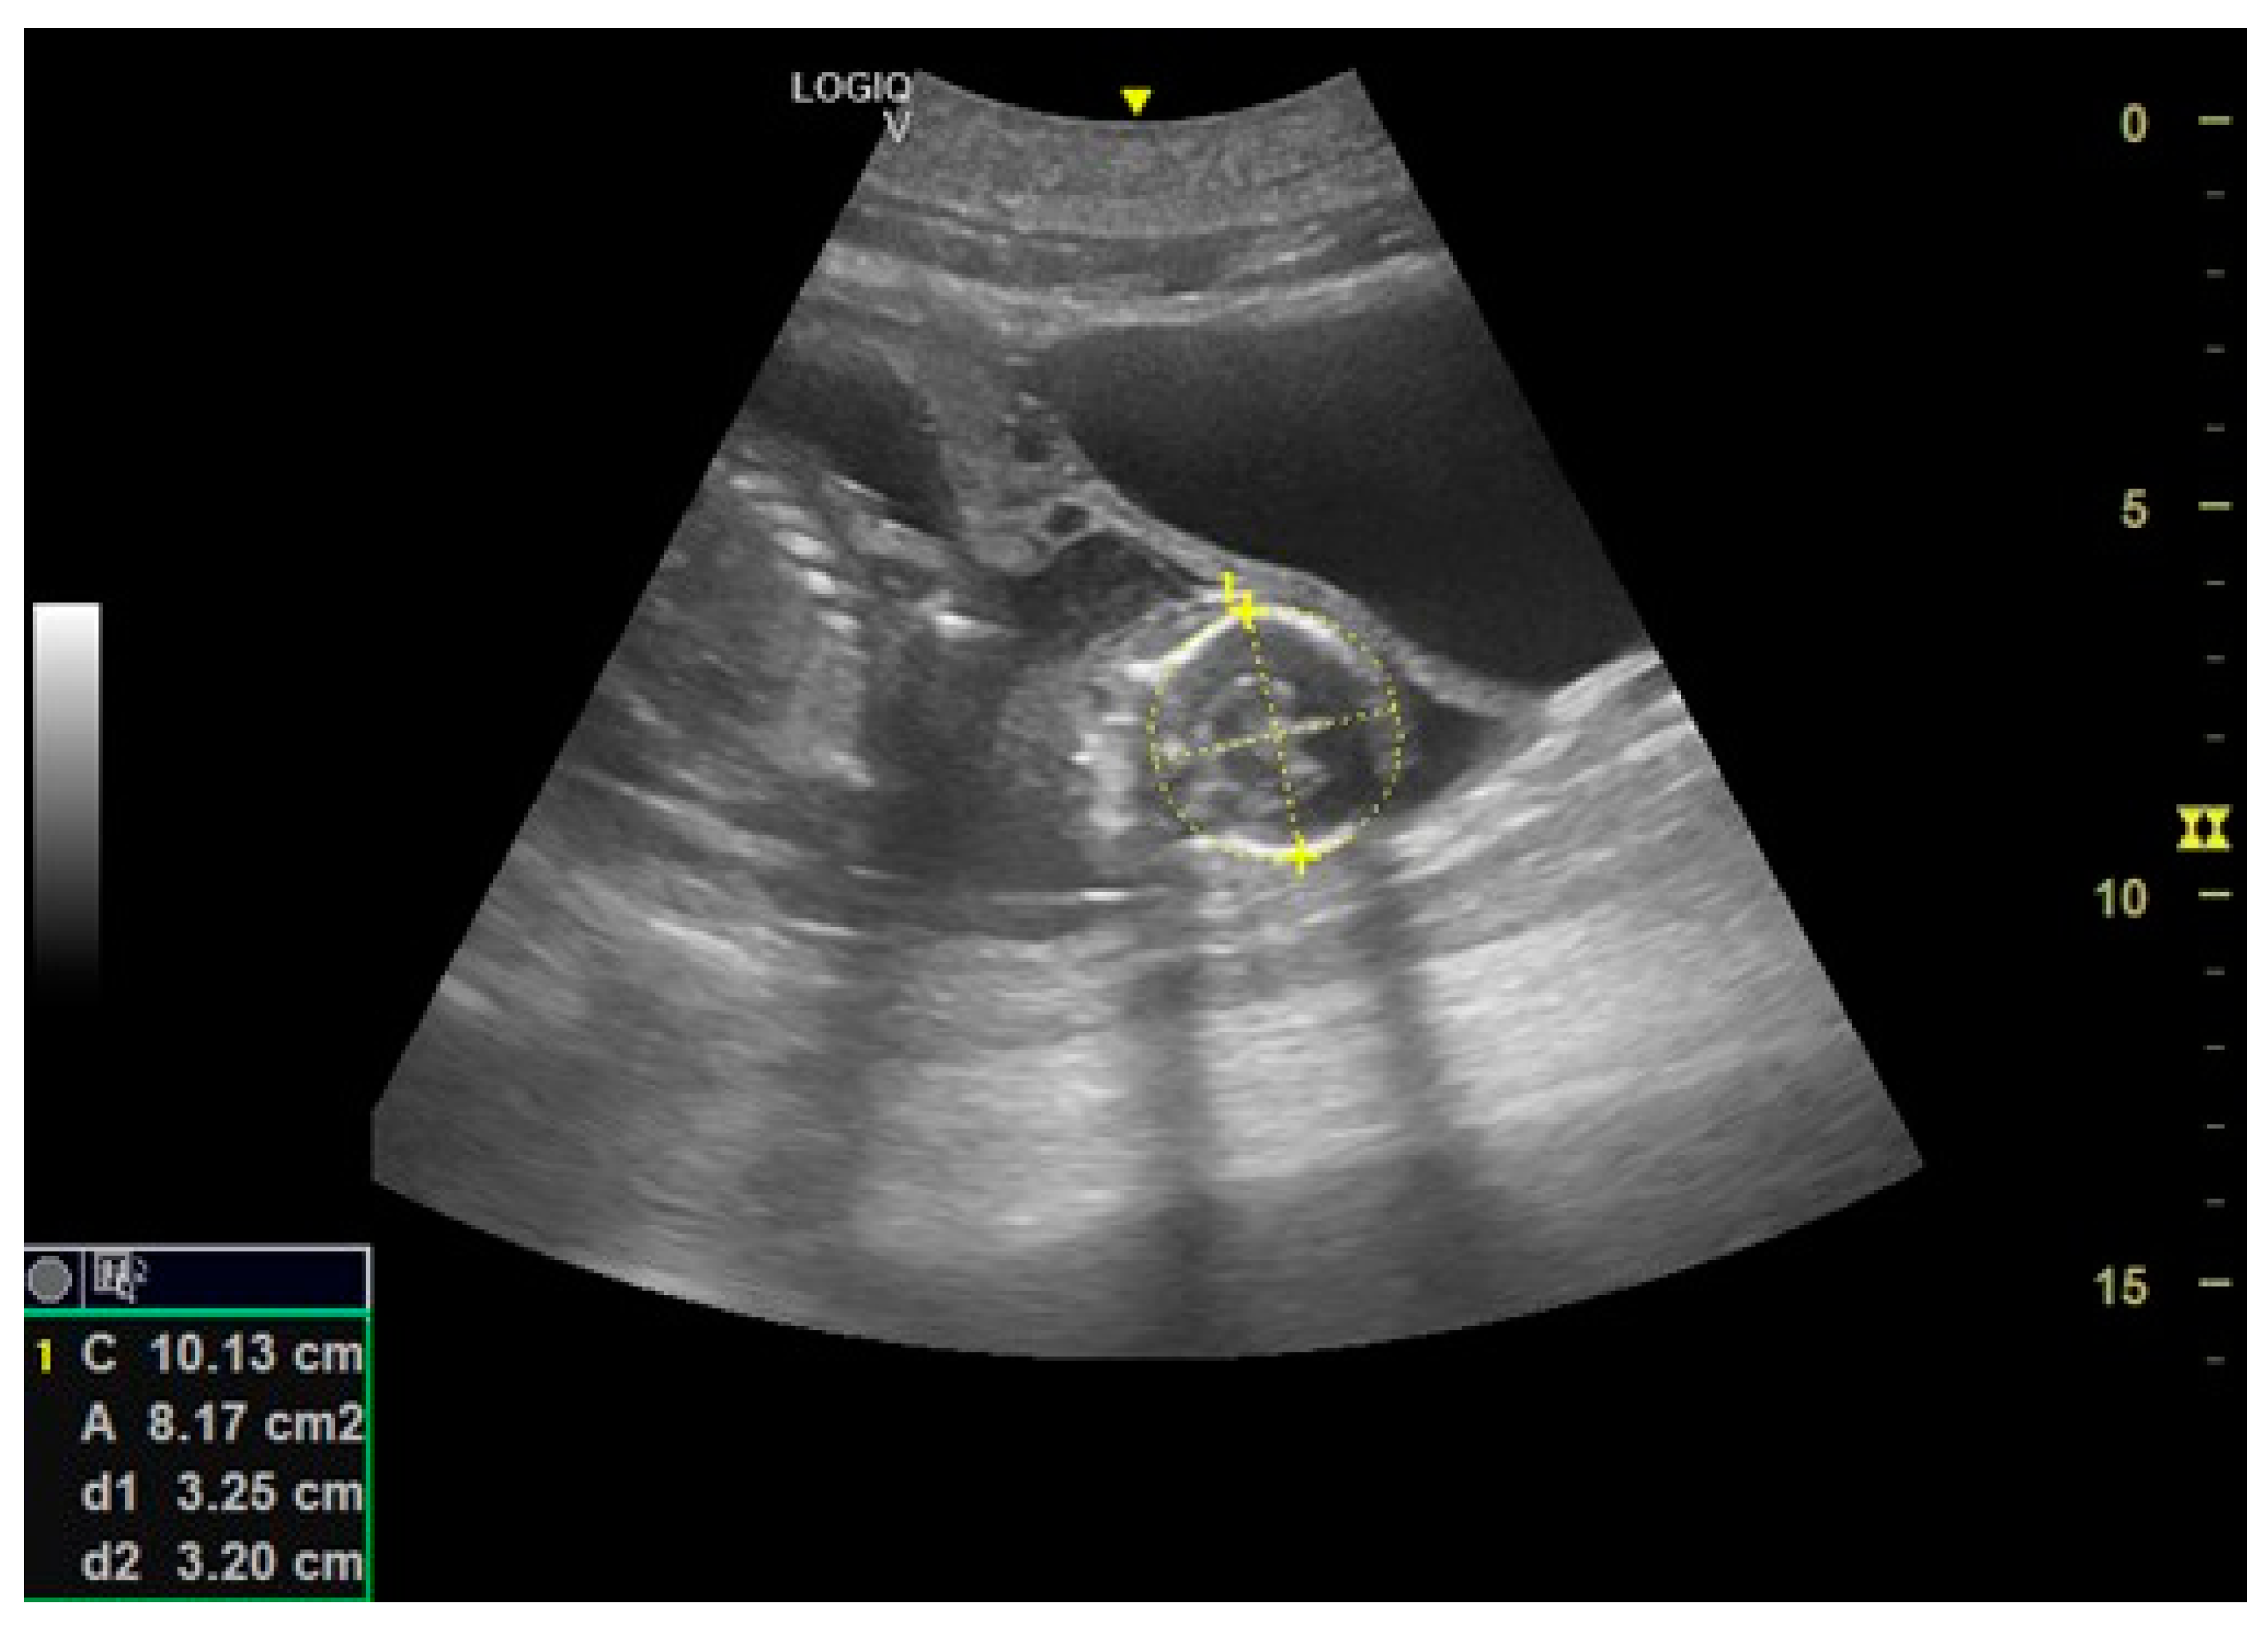

- Day 113 ± 4 post-ovulation: The embryonic vesicle was first recognizable in the uterine cavity as a roundish structure with an average diameter of 1.71 cm with an anechoic content. In addition, it is possible to recognize the embryo inside it as an elongated hyperechoic structure (Figure 2). Thanks to these findings, it has been possible to make a diagnosis of pregnancy.